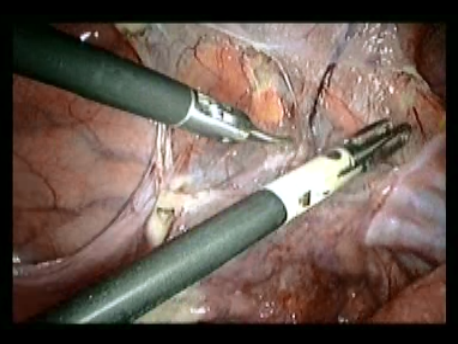

Endometrial cancer is cancer of the lining of the uterus. The treatment of early stage endometrial cancer is a simple hysterectomy and, in select cases, pelvic lymphadenectomy (specialized organs which drain tissue fluid). Laparoscopic surgery is the route of choice for treatment of endometrial cancer.